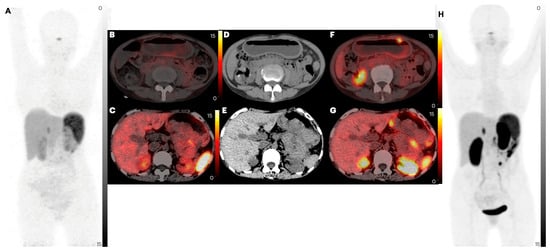

2.2. Comparison of Lesion Detection and Uptake between [68Ga]Ga-DOTANOC and [68Ga]Ga-DATA5m-LM4

2.2.1. Primary Tumor

2.2.2. Lymph Node Metastases